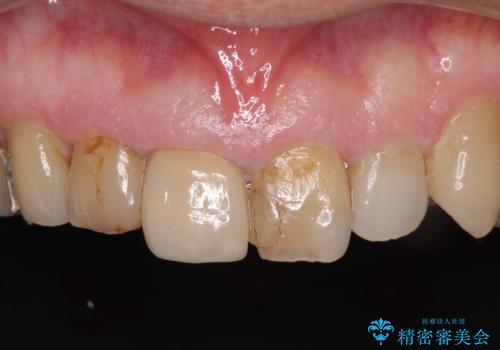

- 前歯がぐらつくことを主訴にご来院された患者様です。ご本人は抜歯と考えており、インプラント以外の治療をご希望でした。しかしながらぐらついていた原因は、古い差し歯が取れかけていたことでした。

遠方から通院されること、仕事上短期間で治療したいとのことを考慮して、残っている歯はかなり小さいものの、保存すべきと判断して当日処置から行いました。

西日本から新幹線でご来院された患者様です。前歯は都内の医院でやりたいとのことで、はるばる通院してくださいました。通院回数が最小限になるよう工夫しました(1回あたりの時間は長くなります)。

残っている歯が小さいと、差し歯はぐらつきやすくなりますが、その形態によっては抜歯を回避できることがあります。